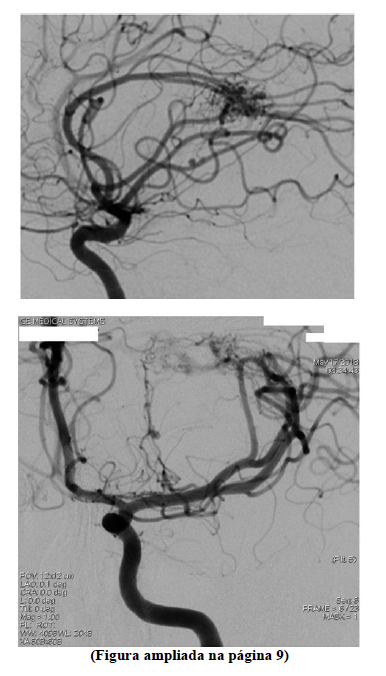

Um homem de 42 anos de idade é levado à emergência pelos vizinhos, que relatam que o encontraram caído, sem conseguir movimentar o lado direito ou falar. A mãe relatou que, há dois dias, o paciente iniciou com cefaleia e nucalgia, tratadas como quadro hipertensivo na unidade básica de saúde. Ao exame: PA = 137 mmHg x 79 mmHg, FR = 16 ipm, FC = 96 bpm, SaO2 = 98% em ar ambiente e glicemia capilar = 125 mg/dL, com paciente alerta, afásico, com hemiparesia direita (força grau 1), paralisia facial central à direita e pupilas isocóricas e fotorreagentes, obedecendo a comandos verbais à esquerda. Uma tomografia do crânio sem contraste evidenciou hemorragia intraparenquimatosa em núcleos da base à esquerda com pequeno efeito compressivo em ventrículo lateral esquerdo, sem desvio de linha média. Foi realizada uma angiografia digital.

Com base nesse caso clínico e nas imagens da angiografia digital apresentadas e conhecimentos médicos correlatos, julgue os itens a seguir.